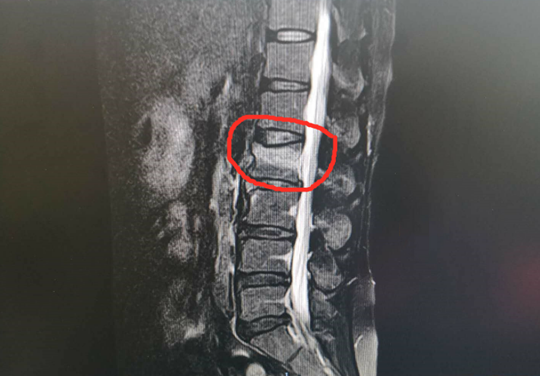

77岁的王大爷因轻微扭伤导致腰背部疼痛并且活动受限,一开始他以为是一般的腰肌劳损,休息休息就能好,可是一个月下来,疼痛一点都没减轻,配了膏药和服用止痛药也不见效,症状反而越来越重,起床翻身时疼痛更明显,王大爷赶紧到betway在线登陆,一拍片,结果是腰椎骨质疏松性椎体骨折,王大爷很纳闷,怎么没摔跤就骨折了呢?原来,中老年人常见的骨质疏松症,往往不需要太大外力就能发生骨折。

针对王大爷的顾虑,betway在线登陆脊柱科张冶医生耐心告诉他,像他这种情况需要手术治疗,因为保守治疗会因长期卧床,活动量减少,骨量进一步丢失,导致再度骨折,形成恶性循环,许多患者最终因长期卧床并发症而死亡。

这些也是患者关心的问题。张冶医生告诉王大爷,这个手术是微创手术,不是传统意义上开大刀的方法,手术切口很小、时间也短,只需向骨折的椎体内“打一针”,注入神奇的专用“骨水泥”,通过骨水泥将骨折块锚定,疼痛就能迅速缓解,术后第二天,即能下床活动,生活能自理,很好地避免传统治疗长期卧床所引起的严重并发症,减轻患者痛苦,也减轻家人负担。